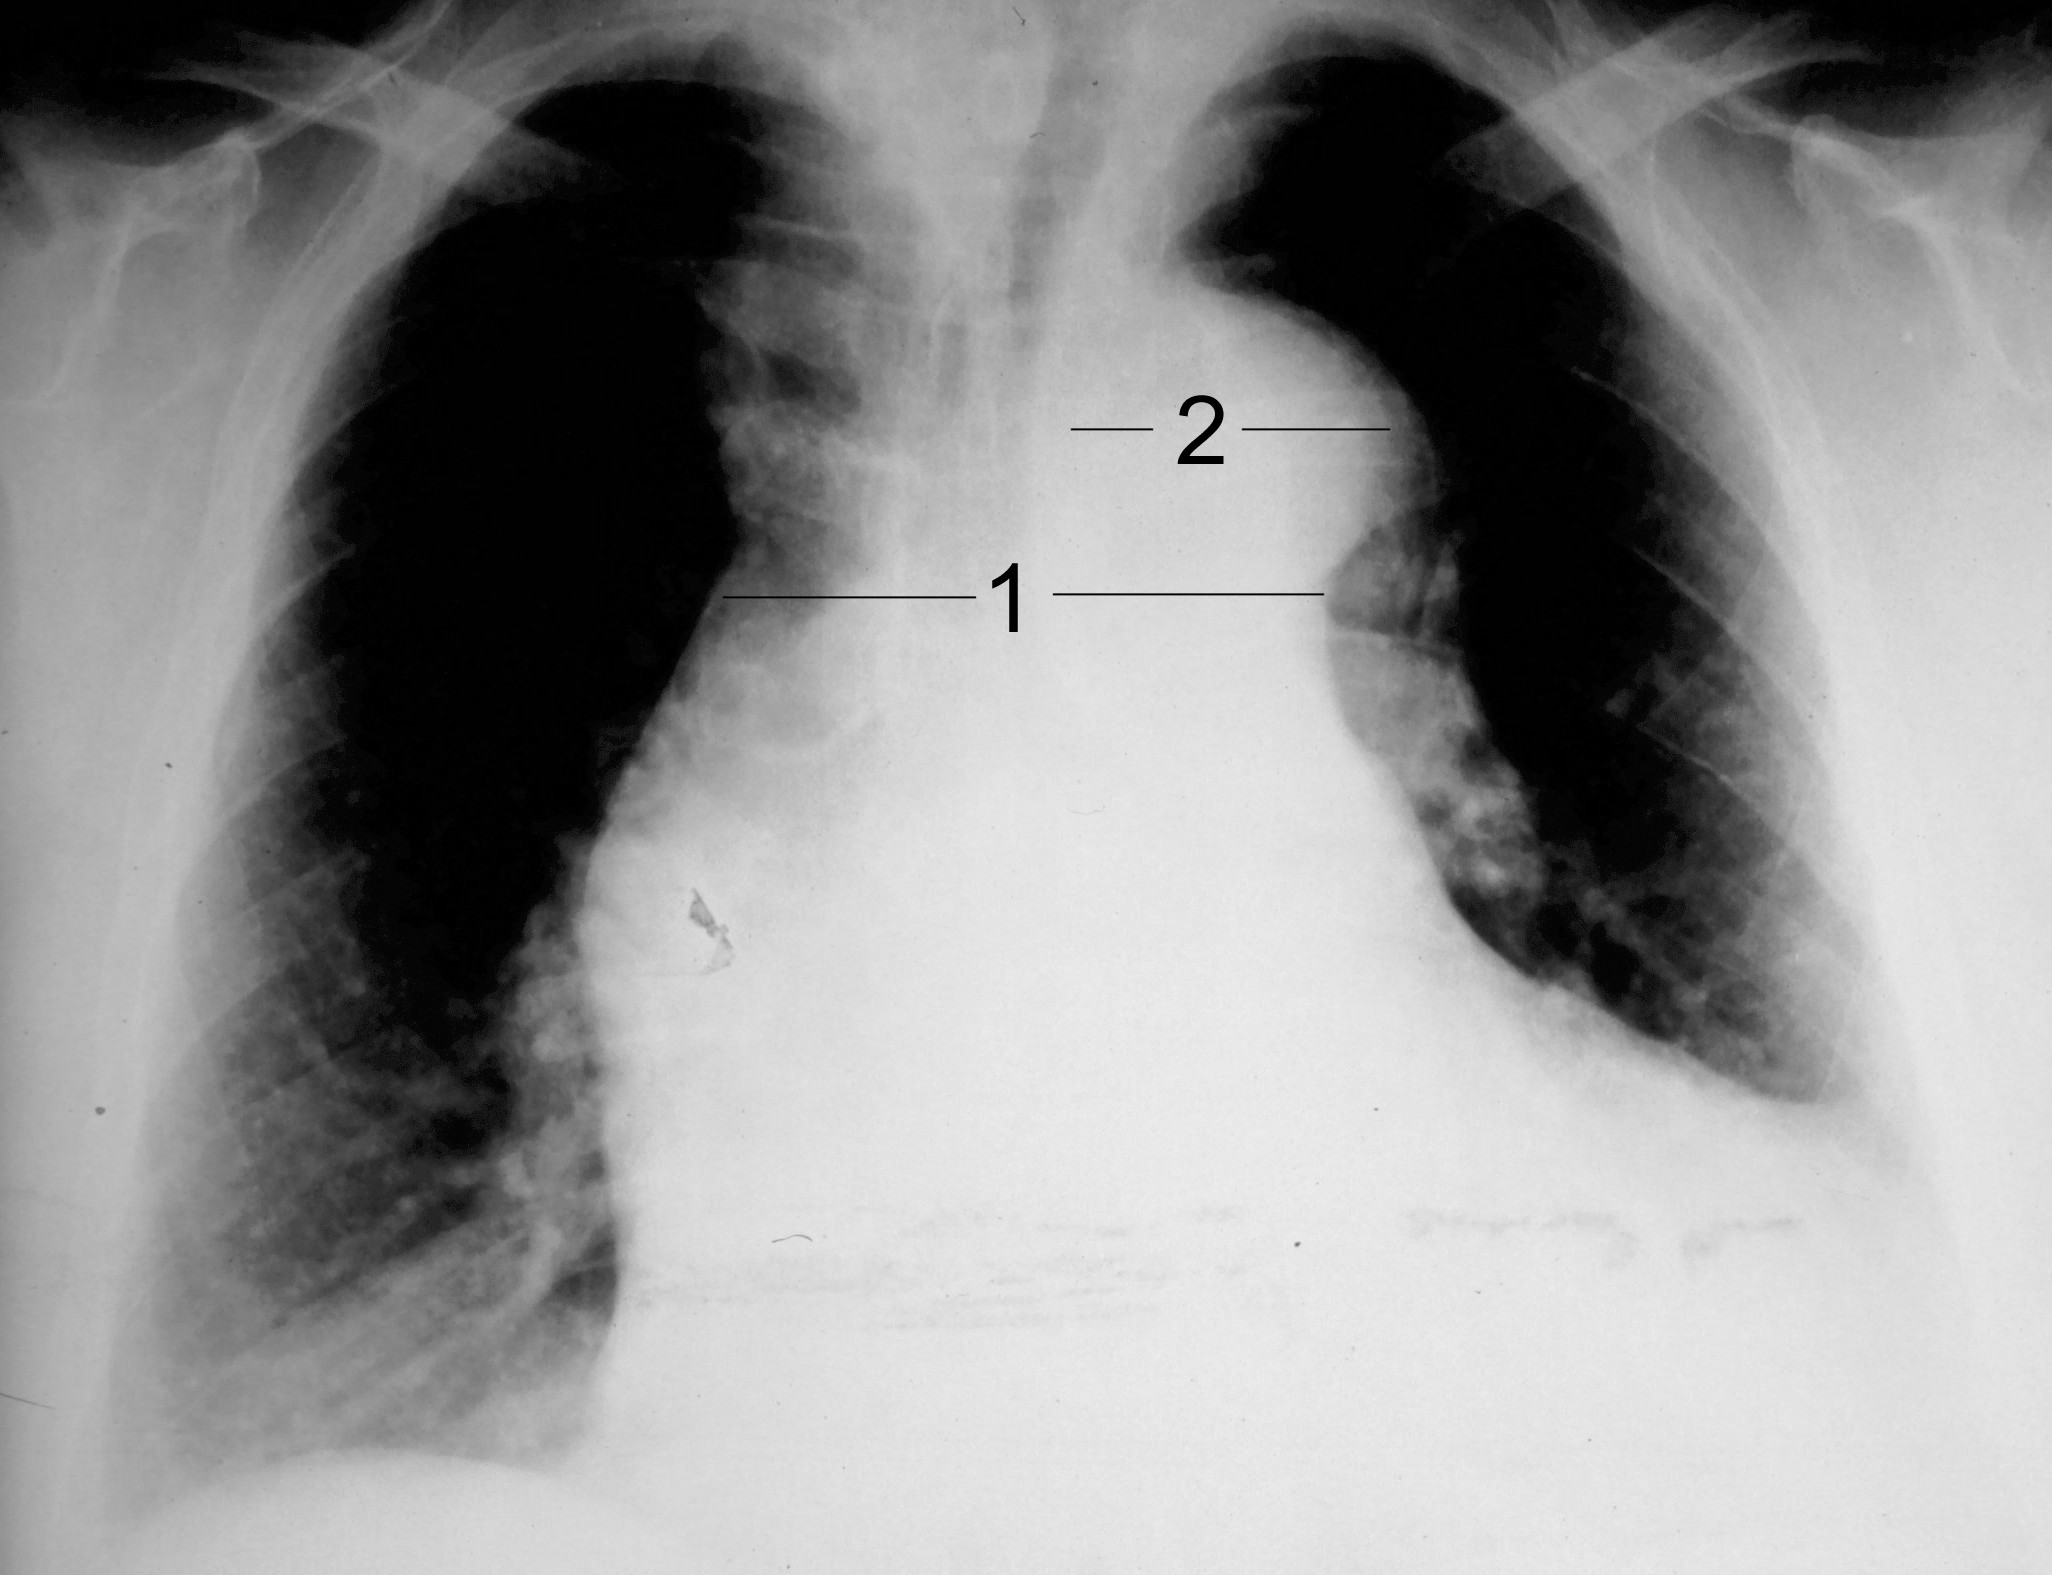

CXR showing widened mediastinum and porminent aortic knob

| current | 17:43, 19 May 2016 | ![]() | 2,052 × 1,575 (291 KB) | Alvarez13 (Talk | contribs) | CXR showing widened mediastinum and porminent aortic knob |